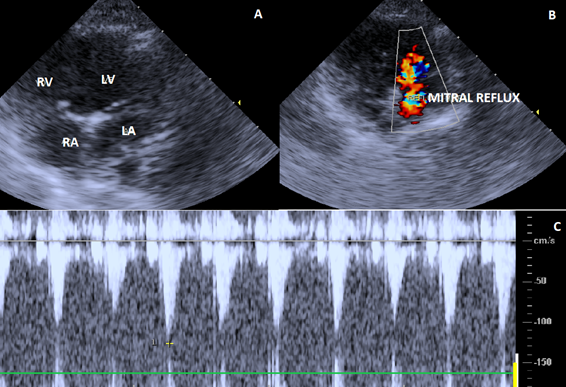

The echodoplercardiogram showed changes in the tricuspid (Figure 2), mitral (Figure 3) and pulmonary (Figure 4) valves. Due to the presence of pulmonary artery pressure greater than 25-30mmHg (35 mmHg), a diagnosis of pulmonary hypertension was definided.

Figure 3 Echocardiographic image showing right parasternal short-axis view of the mitral valve. A. Mitral valve with normal appearance and movement of its valves. B. Doppler study and color flow mapping showing severe valve insufficiency. C. Spectral doppler tracing with mitral valve regurgitation.